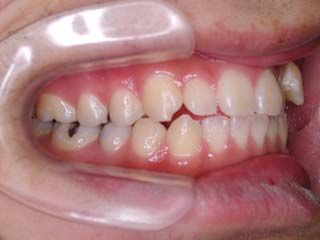

主訴:噛み合わせが悪い 顎が痛い 首が痛い

診断名:顎関節症を伴う叢生

年齢:20歳

はならび自体は僅かな叢生が見られるだけなのですが、実はほとんどの歯が噛めていません。奥歯ばかりで強く噛んでいる状態です。また、顎関節症でよく見られる首、肩の具合が悪い という症状も見られました。かみ合わせとの関連性については不明ですが、適正な咬合構築に伴って、これらの症状が改善する事をよく経験します。